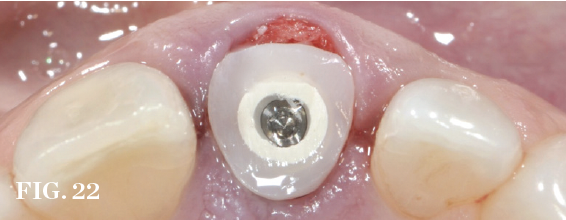

(22.) Prefabricated custom healing abutment. Note the facial cutback to allow for the addition of a connective tissue graft to level the gingival margin with the contralateral dentition.

Figure 22

Guided Bone Regeneration

Management of the defect between the implant and socket walls and contour enhancement beyond the facial/buccal socket wall are almost always required in immediate placement approaches. Bone grafting of the residual horizontal defect and, at times, buccal contour augmentation are used to compensate for expected buccal plate changes resulting from extraction, especially when the bone morphotype is thin (Figure 19 through Figure 22). Soft-tissue grafts can be used to further support stable facial tissues, but they will not completely prevent changes in bone volume that are associated with postextraction remodeling (Figure 23 and Figure 24).